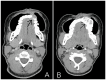

Ewing sarcoma (ES) is a small, round, blue cell malignant neoplasm that rarely occurs in the craniofacial skeleton, with presentation in the maxilla being exceedingly rare. We report the case of a 14-year-old girl with a two-year history of slowly progressive facial swelling that has recently become greatly enlarged. Imaging revealed an aggressive expansile left maxillary lesion with soft-tissue involvement and internal calcifications. Surgical resection was performed, and histopathological analysis showed sheets of homogenous round cells with minimal cytoplasm and round nuclei. Immunohistochemical staining for CD99, CD56, and NKX2.2 was positive, while staining for epithelial, muscle, and neural markers was negative, thereby confirming the diagnosis of ES. This case highlights the diagnostic difficulty of ES in unusual sites such as the maxilla, where it can mimic odontogenic or fibro-osseous lesions. Early diagnosis with histopathology and immunohistochemistry is important for appropriate management, which usually includes surgical resection followed by chemotherapy.